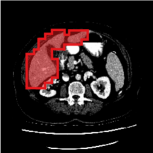

Consider a three-dimensional object within a volume. It is straightforward to produce a 3D bounding box of the object by finding its extreme points in the three coordinate axes. While this 3D bounding box will be tight in the 3D sense, its rectangular cross-sections will not, in general, remain tight with respect to the planar cross-sections of the volume. Fig. 1 illustrates such a case for the task of liver segmentation in a CT volume. In the Experiments section we show that the success of existing 2D weakly-supervised segmentation methods relies on the bounding boxes being tight and therefore the tightness of the individual 2D bounding boxes should be corrected before training and applying a segmentation CNN.

(a)

(b)

(c)

(d)

The global bounding box tightness prior mentioned above assumes that each of side of the box is sufficiently close to the target region. This means that for any region shape, each vertical or horizontal line inside the bounding box will cross at least one pixel belonging to the target region. This condition does not hold when the provided annotation comes as a 3D bounding box which is represented as a series of per-slice non-tight 2D bounding boxes. In this case, there will exist vertical or horizontal lines shown as stripes in Fig. 1 (d), that will lie outside of the actual object boundary. In the Experiments section we demonstrate the poor performance of the weakly-supervised approach from [5] when the user-provided bounding box is much wider than the true object of interest.